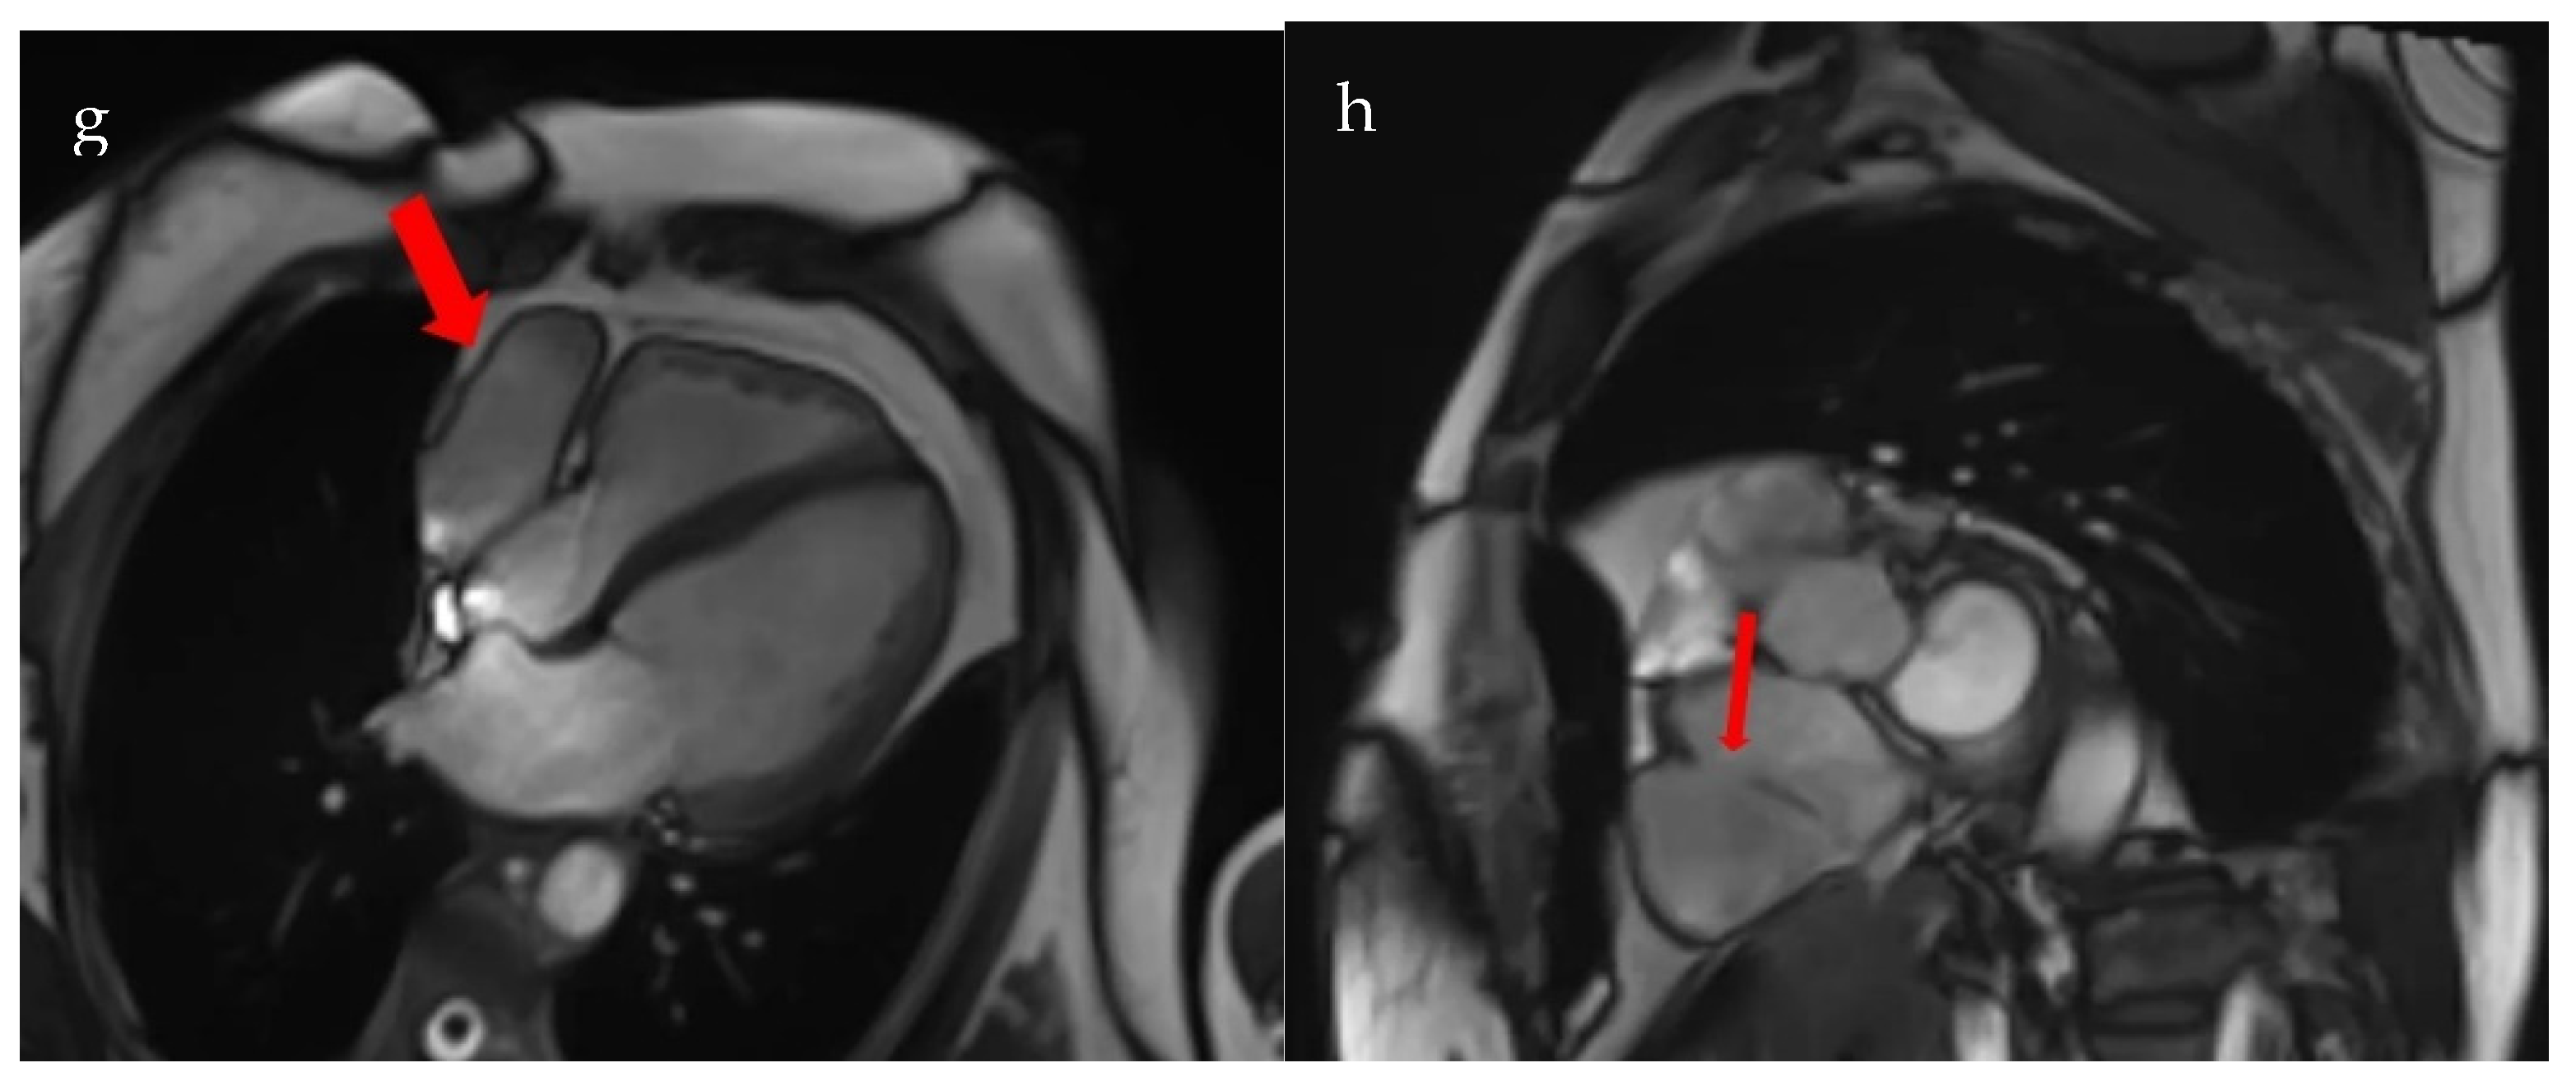

Follow-up transthoracic echocardiography revealed an enlargement of the previously noted structure, now measuring 36 × 49 mm, producing the systolic collapse of the right atrium. A saline contrast study confirmed the communication between the right atrium and the pericardial space (Figure 4).

Figure 4.

Transthoracic echocardiography. (a). Subcostal view: right atrial diverticulum 36 mm × 49 mm; (b). 4-chamber apical section: right atrial diverticulum with systolic collapse of the right atrium (red arrow); (c). Saline contrast test—subcostal section: communication between right atrial diverticulum and right atrium (red arrow) (RA—right atrium; RV—right ventricle).